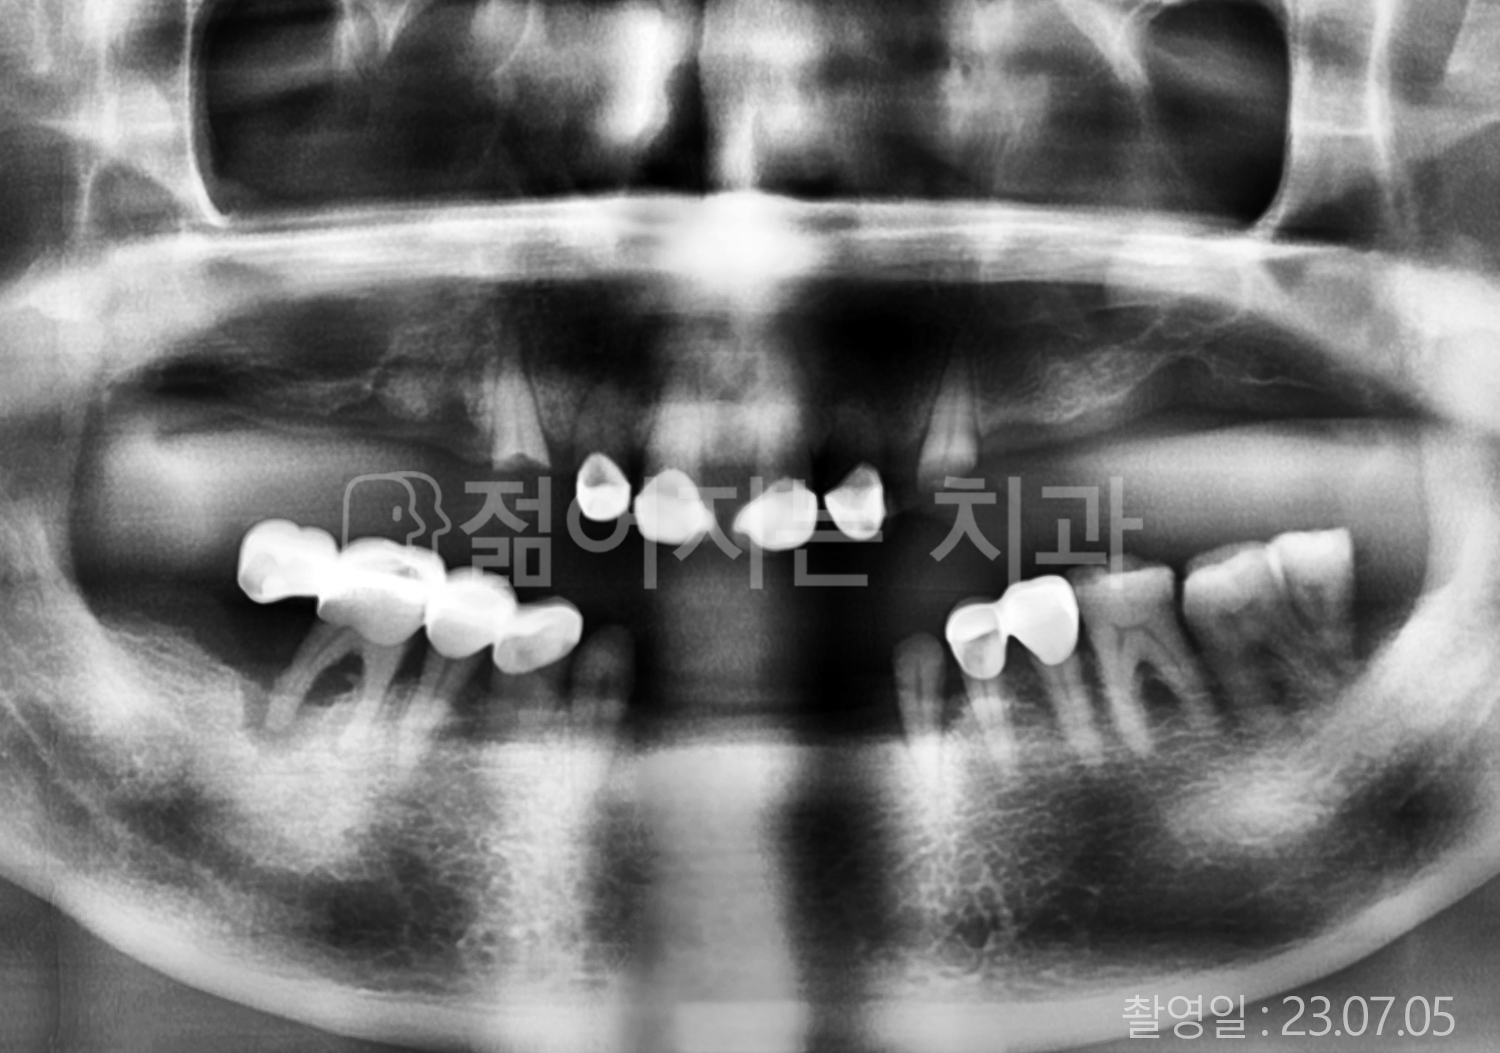

• 80대 전체치아 10개 이상 임플란트

• 60대 고혈압, 당뇨, 고지혈증 전체치아 10개 이상 임플란트

• 60대 전체치아 10개 이상 임플란트

• 60대 고혈압, 고지혈증 전체치아 10개 이상 임플란트

• 50대 고혈압, 당뇨, 고지혈증 전체치아 10개 이상 임플란트

• 70대 골다골증, 파킨스병 전체치아 10개 이상 임플란트

• 40대 전체치아 10개 이상 임플란트

• 60대 골다골증 전체치아 10개 이상 임플란트

• 40대 고혈압 전체치아 10개 이상 임플란트

• 50대 전체치아 10개 이상 임플란트

• 70대 전체치아 10개 이상 임플란트